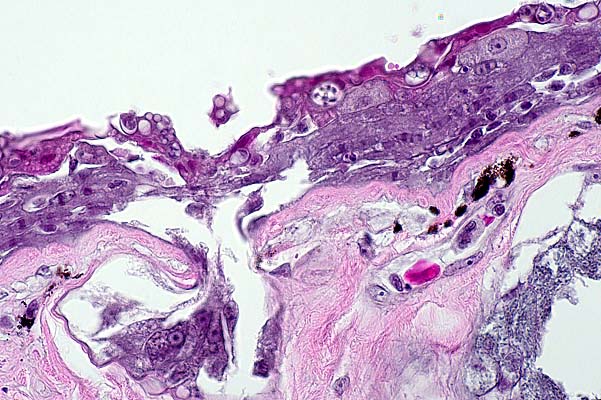

- Case 29-1. Dermis. Variably pigmented spindle shaped

cells contain anisotropic crystalline material when viewed under

polarized light.

- Sections of skin containing an expansile, nonencapsulated,

multilobular, pigmented dermal mass which extends to both lateral

and ventral borders in some sections. The mass is composed of

whorls, interlacing bundles, nests and fascicles of a uniform

population of spindle cells on a fine fibrovascular stroma. The

cells are spindle to stellate with indistinct cell borders, moderate

amounts of eosinophilic fibrillar cytoplasm with varying amounts

of coarse to fine golden brown/olive green pigment granules.

The nuclei are ovoid to polyhedral with coarsely clumped chromatin

and a single, variably distinct, round, magenta nucleolus. The

mitotic index is less than l/HPF. Pigment granules are birefringent

on polarized light.